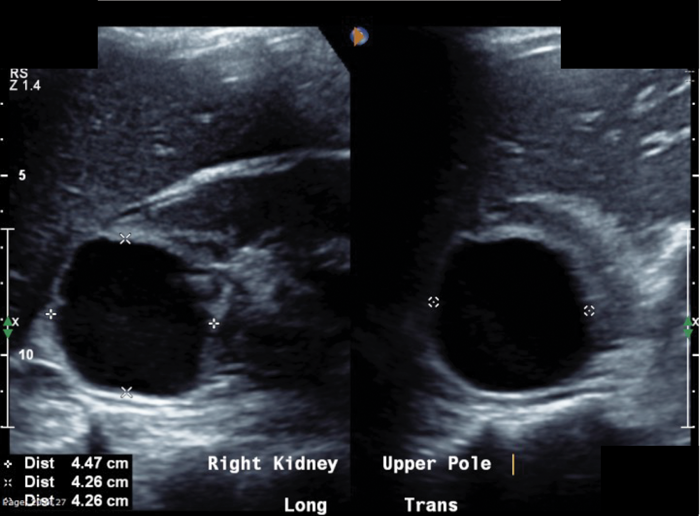

A 34-year-old lady is referred from the medics with right-sided loin pain and urosepsis. An initial ultrasound scan was arranged, followed by a subsequent CT scan. These scans did not show any renal / ureteric stone, but selected images are shown to the left.

A well-defined cystic structure in the upper pole of the right kidney. The cystic structure had calcification within the wall. CT demonstrated a fluid density mass within the cyst, with an irregular coarse foci of wall calcification. There is a solitary gas locule within the superior aspect of the cyst.